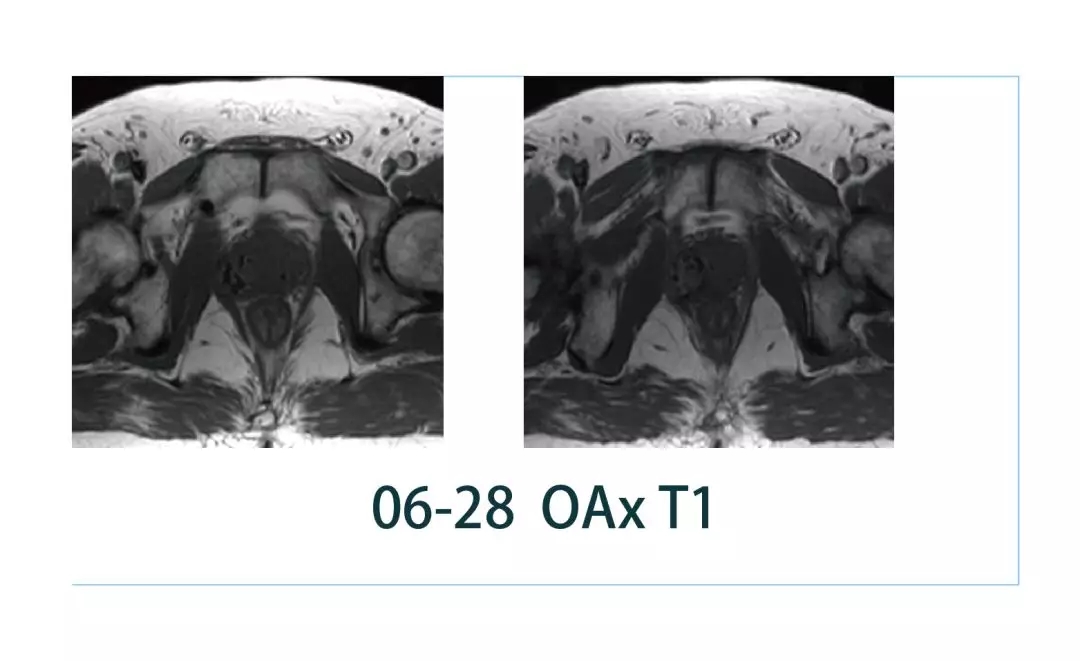

【朗润影像档案】磁共振影像病例分享(编号20190308)